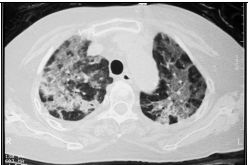

4. 60歲B細胞淋巴瘤病人,化療中出現發燒、乾咳和喘,其胸部電腦斷層如圖,下列何種感染最可能? (A) Pneumocystis jirovecii (B) Hemophilus influenzae (C) Nontuberculosis Mycobacterium (D) Cryptococcus neoformans (E) Pseudomonas aeruginosa